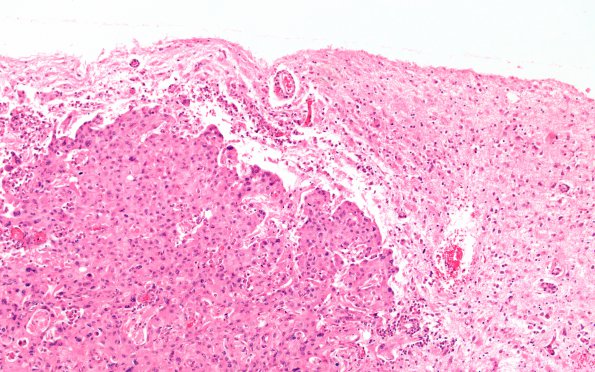

1B2 Metastases (Case 1) G H&E 10X 4

The tumor reaches but does not transgress the pial surface. (H&E)